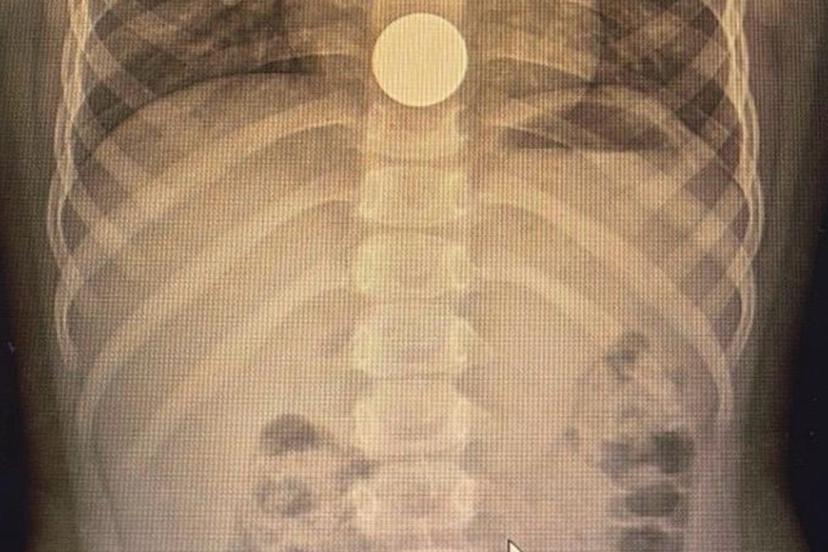

Çocuklarda sık karşılaşılan risklere değinen Özkaya "Günlük hayatta çocuklarda sık karşılaşılan yabancı cisim yutulması, kimyasal madde içilmesi ve solunum yollarına yabancı cisim kaçması önemli sağlık sorunları arasında yer almaktadır. Özellikle ilk üç yaşındaki çocuklar, yerde buldukları nesneleri ağızlarına götürme eğilimindedir. Madeni paralar, disk piller, iğneler ve küçük oyuncak parçaları çocuklar tarafından yutulabilmekte; bu maddeler yemek borusuna ya da solunum yollarına kaçabilmektedir. Bu tür durumlarda ailelerin olaya şahit olmaları hâlinde çocuğun ağzını kontrol etmeleri, yutma şüphesi varsa vakit kaybetmeden en yakın sağlık kuruluşuna başvurmaları gerekmektedir." dedi.

Solunum yollarına yabancı cisim kaçmasının da önemli bir risk olduğuna dikkat çeken Özkaya "Solunum yollarına yabancı cisim kaçması da günlük hayatta sık karşılaşılan ve hayati tehlike oluşturabilen durumlardan biridir. Özellikle üç yaşına kadar olan çocuklara çerez, fındık, fıstık, çekirdek gibi sert gıdaların verilmemesi gerekmektedir. Bu gıdalar solunum yollarına kaçarak ciddi nefes darlığına neden olabilmektedir. Böyle bir durumla karşılaşıldığında, mümkünse Heimlich manevrası uygulanmalı ve 112 Acil Servis eşliğinde en yakın sağlık kuruluşuna başvurulmalıdır. Bu tür vakaların operasyon gerektirebileceğine dikkat çekilerek, özellikle yemek borusunda kalan disk pillerin son derece tehlikeli olduğu vurgulanmaktadır. Disk piller, çocukta belirgin bir şikâyet olmasa bile kısa sürede yemek borusunda yanıklara ve delinmelere yol açabilmekte, hayati risk oluşturabilmektedir. Bu nedenle acil olarak ameliyathane ortamında çıkarılmaları gerekmektedir." şeklinde konuştu.